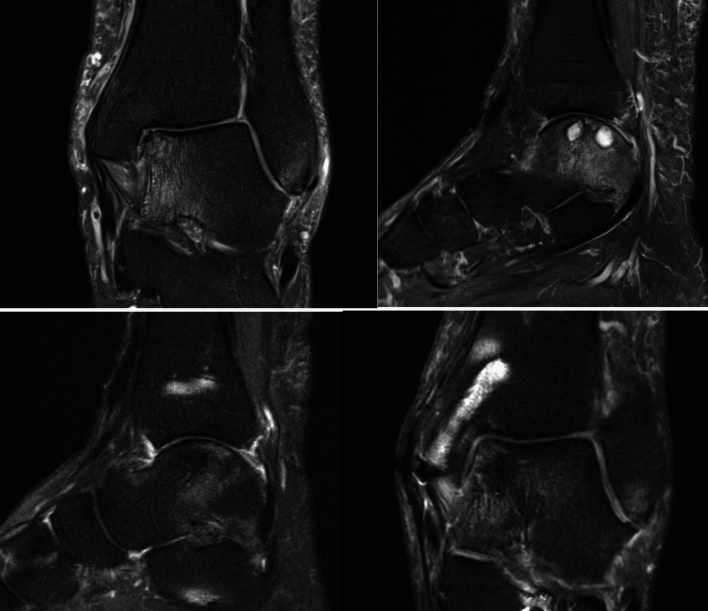

An important radiological indicator for the success of the procedure is the progressive coverage of bone stock with cartilage and a low water signal in t2-sequences in MR imaging. This relates with cartilage cell outgrowth, proliferation, and differentiation (Fig. 4). Indirect radiological parameters are the amount of bone marrow edema, joint effusion and synovialitis. Direct and indirect radiological parameters are used to evaluate AOSS scores.

Fig. 4.

Coronary and sagittal slices of t2 sequenced MRI preoperatively and postoperatively after treatment of an osteochondral defect with subchondral cysts in the medial talus with autologous cancellous bone from the proximal tibia and minced cartilage along with fibrin fixation after osteotomy of the distal tibia